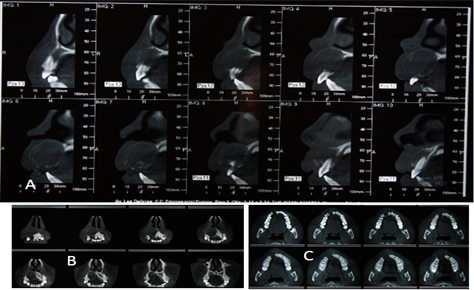

Figura 6. Tomografía de haz cónico.

Imagen (a) vista frontal y oclusal (b) cortes transaxiales de tomografía de haz cónico donde se evidencia tamaño y cuanto involucra los órganos dentales con una imagen hipodensa bien definida.

Figura 7. Tomografía de haz cónico.

Imágenes (a) imágenes hipodensas e hiperdensas que orientan la magnitud y volumen de la lesión (b) cortes axiales zona maxilar, con imágenes hipodensas e hiperdensas que orientan a la planificación quirúrgica.